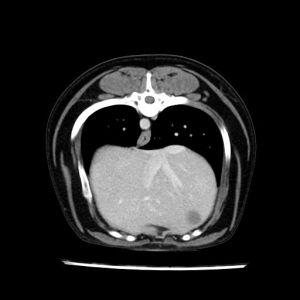

La lesione focale epatica , la ceus,la Tac e il chirurgo .